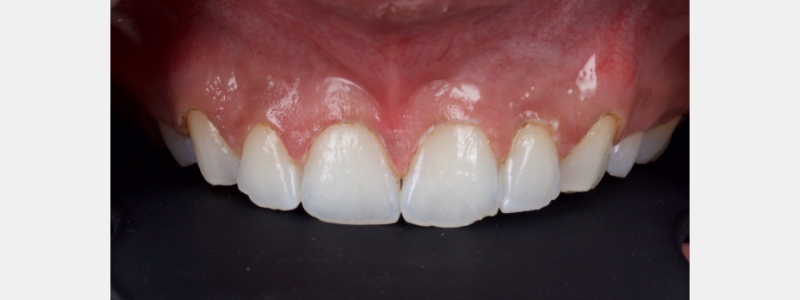

In this case, a young patient in his early 20s presents with discolored central incisors, multiple diastemas, and a canted incisal plane (Fig. 23).

A clear PVS stent was fabricated from a digital wax-up and filled with flowable composite (Fig. 24).

I prefer an opaque flowable composite for this application because a regular flowable composite tends to be quite translucent, making the underlying tooth structure visible, which distracts many patients. The flowable composite was polymerized, and the stent was removed.

The esthetics were assessed by the patient, and some adjustments were made to the distal line angles of the lateral incisors. When the patient was satisfied with the appearance, another sectional digital scan of the modified mock-up in the patient’s mouth was taken and stitched into the original scan to form the final mock-up (Figs. 25 and 26).